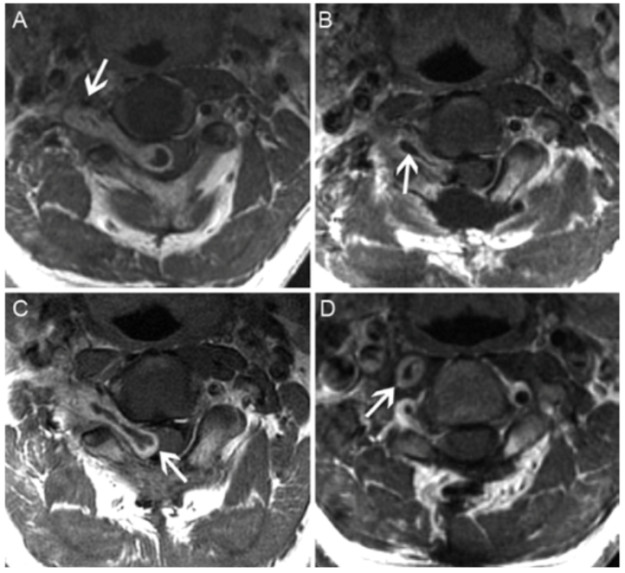

90例患者中,51例(56.7%)男性和39例(43.3%)女性;年龄7-77岁,平均44.5岁。其中哑铃状肿瘤62例(68.9%);全切除59例(65.6%)。28例非哑铃状肿瘤均做到GTR。在术后150个月的随访期间,GTR组仅1例复发,MRI表现肿瘤逐渐增加(8.9mm)。次全切除组的复发患者,在20.3个月的随访期间,肿瘤大小的平均增加百分比为47.5%±33.1%,平均生长速率为每年5.8±4.6mm。然而,对无肿瘤再生长患者的48.4个月随访期间,残留肿瘤的大小自然缩小8.3%±11.1%(图1)(表1)。

图1. 1例患者MRI资料。A.术前MRI-T1加权轴向位增强图像显示,C2-3处哑铃状肿块,于硬膜下和硬膜外生长并向椎旁延伸(Eden II型);椎动脉(箭头)受肿瘤挤压,动脉周围受累区<180°。B.手术后1周的MRI-T1加权轴向位增强图像显示,右侧C2-3残余肿块中心坏死(箭头)。C.手术后5个月MRI图像显示,残余肿瘤(箭头)增大,突入椎管压迫脊髓。D.第二次手术后9个月MRI图像示,位于椎体右前方的增强的残余病变(箭头)。